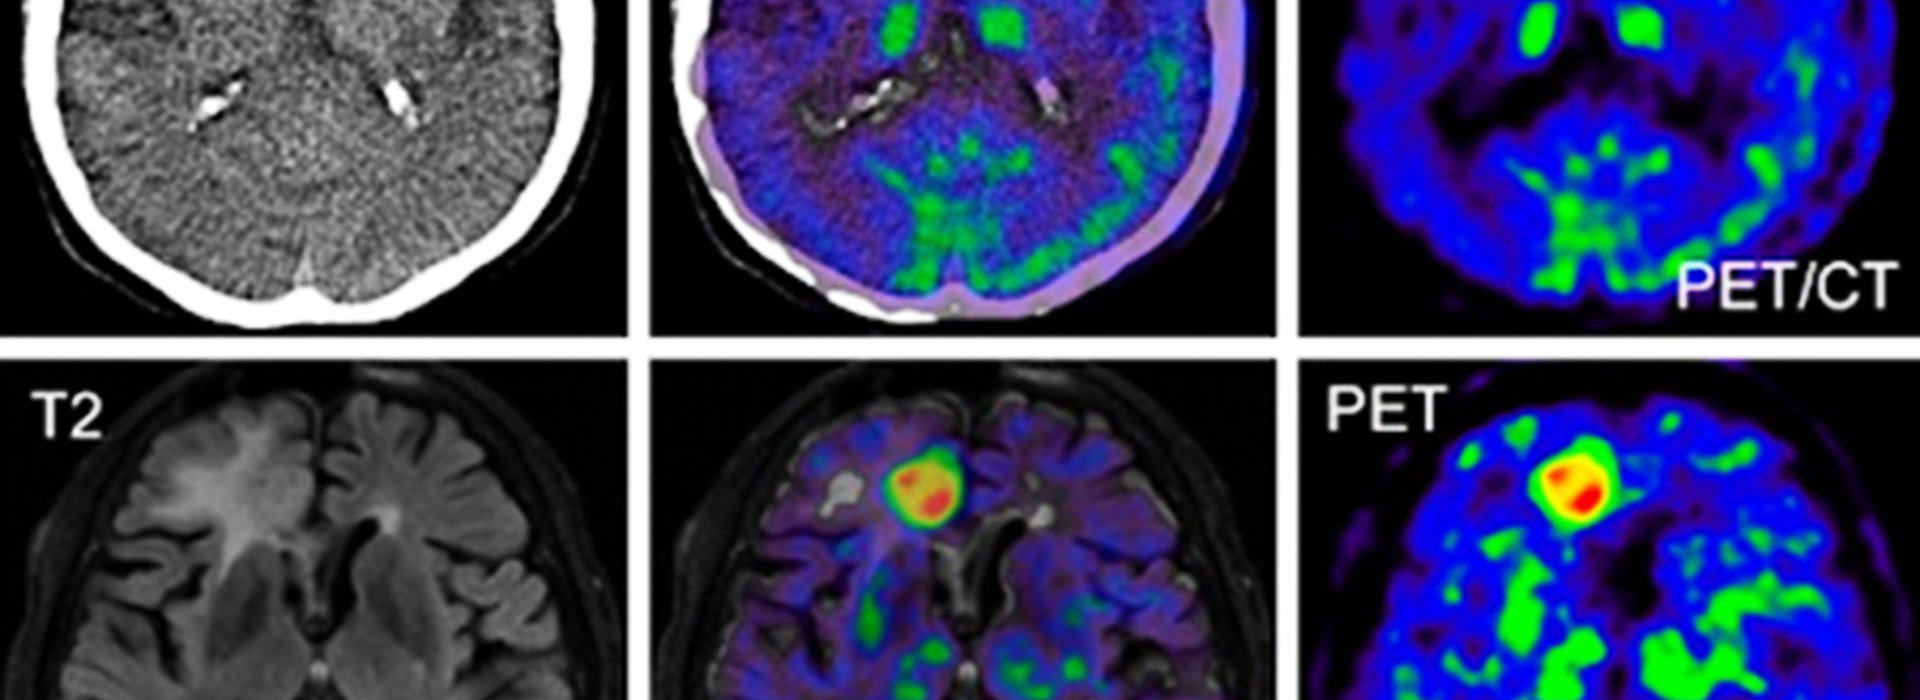

Η πολυετής επικοινωνία μας με, κλινικές, νοσοκομεία, ιατρούς και πελάτεςαπό όλο τον κόσμο, μας έχουν δώσει πολύτιμη εμπειρία και μοναδικό προβάδισμα στην τεχνογνωσία. Με την πάροδο των ετών, οι υπηρεσίες μας στην αντιγραφή και ψηφιοποίηση (scanning) ακτινογραφιών, μαγνητικής και αξονικής τομογραφίας, μαστογραφίας, σπινθηρογραφήματος, αγγειογραφίας, υπερηχοτομογραφίας και κάθε είδους ιατρικής εξέτασης που απεικονίζεται σε φιλμ, έχουν εξελιχθεί σύμφωνα με τις τεχνολογικές απαιτήσεις και συνεχώς εξελίσσονται για να διατηρούν το κορυφαίο επίπεδο ποιότητας και αξιοπιστίας.

- Ψηφιοποίηση Ιατρικών Εξετάσεων

- Αποστολή Ιατρικών Εξετάσεων μέσω internet

- Εκτύπωση Ιατρικών Εξετάσεων